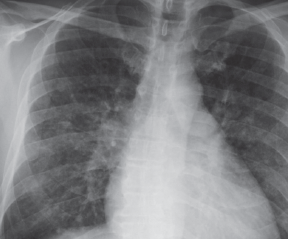

Tuberculosis

05/13/2014

Keta Joshipura Pandit, MD; Aishah Suleiman; Kalpana Gupta, MD

A 19-year-old Hispanic male presented with a 3-month history of productive cough, hemoptysis, and intermittent pleuritic chest pain.